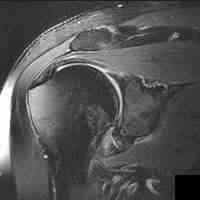

A 27-year-old professional volleyball attacker complains of subtle posterior shoulder pain and a subjective decrease in hitting power. Physical exam reveals normal active elevation, 5/5 strength in shoulder abduction, but notable weakness (3/5) in external rotation with the arm at the side. MRI of the shoulder is ordered. Based on the physical exam findings, where is the isolated neural compression most likely located, and what is the classic associated pathologic finding?

Explanation

The patient exhibits isolated weakness in external rotation (infraspinatus) with preserved abduction (supraspinatus). This indicates suprascapular nerve entrapment distal to the branches supplying the supraspinatus, specifically at the spinoglenoid notch. In overhead athletes, this is classically associated with a paralabral cyst extending from a posterior superior labral tear (SLAP lesion).